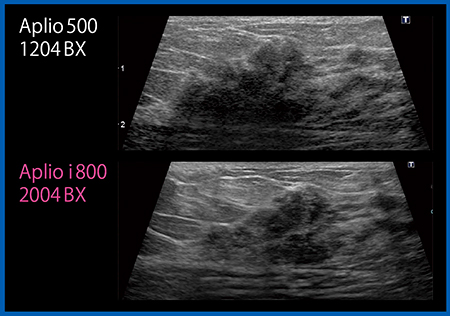

従来,いわゆる視認性と分解能は相反するものであり,どちらを重視するか選択して画質を設定する必要があった。しかし,Aplio iシリーズの新プローブでは,コントラストを上げても,内部構造をつぶすことなく高い分解能を保つことができる。そのため,BI-RADS最新版からは削除されたが,浸潤癌を示唆するような微妙なハローサインも明瞭に描出され,硬癌などの病変が目に留まりやすくなっている(図6)。また,微小病変や石灰化の視認性が上がり,エコーによる精査や広がり診断もしやすくなると考える。

図6 浸潤癌症例の画像比較

Aplio i800ではコントラストが高く,病変の存在,背景のハローサインが明瞭に描出される。